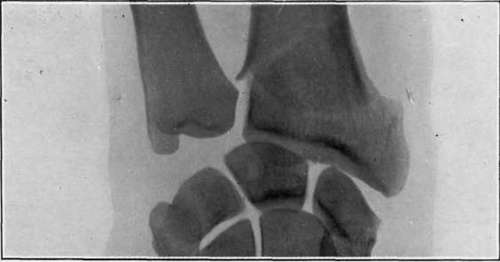

Plate VII.

Fig. II. - 'Motor sprain.' Comminuted fracture of lower end of radius, caused in the same way as fig. I. There was no deformity; the fracture had not been detected until shown by x-rays three months after the injury.